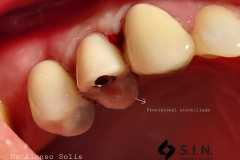

Paciente femenina de 56 años, se presenta a la consulta con puente dental desajustado, con restos alimenticios impactados, se decide realizar un corte de la estructura metálica-porcelana, para conservar piezas restauradas adyacentes, y se coloca un implante dental Marca SIN Implant, realizando provisional para carga inmediata, se espera el proceso de Osteointegración de 4 meses, se observa perfil de emergencia gingival apto, y se procede con la colocación de la corona en Zirconio.